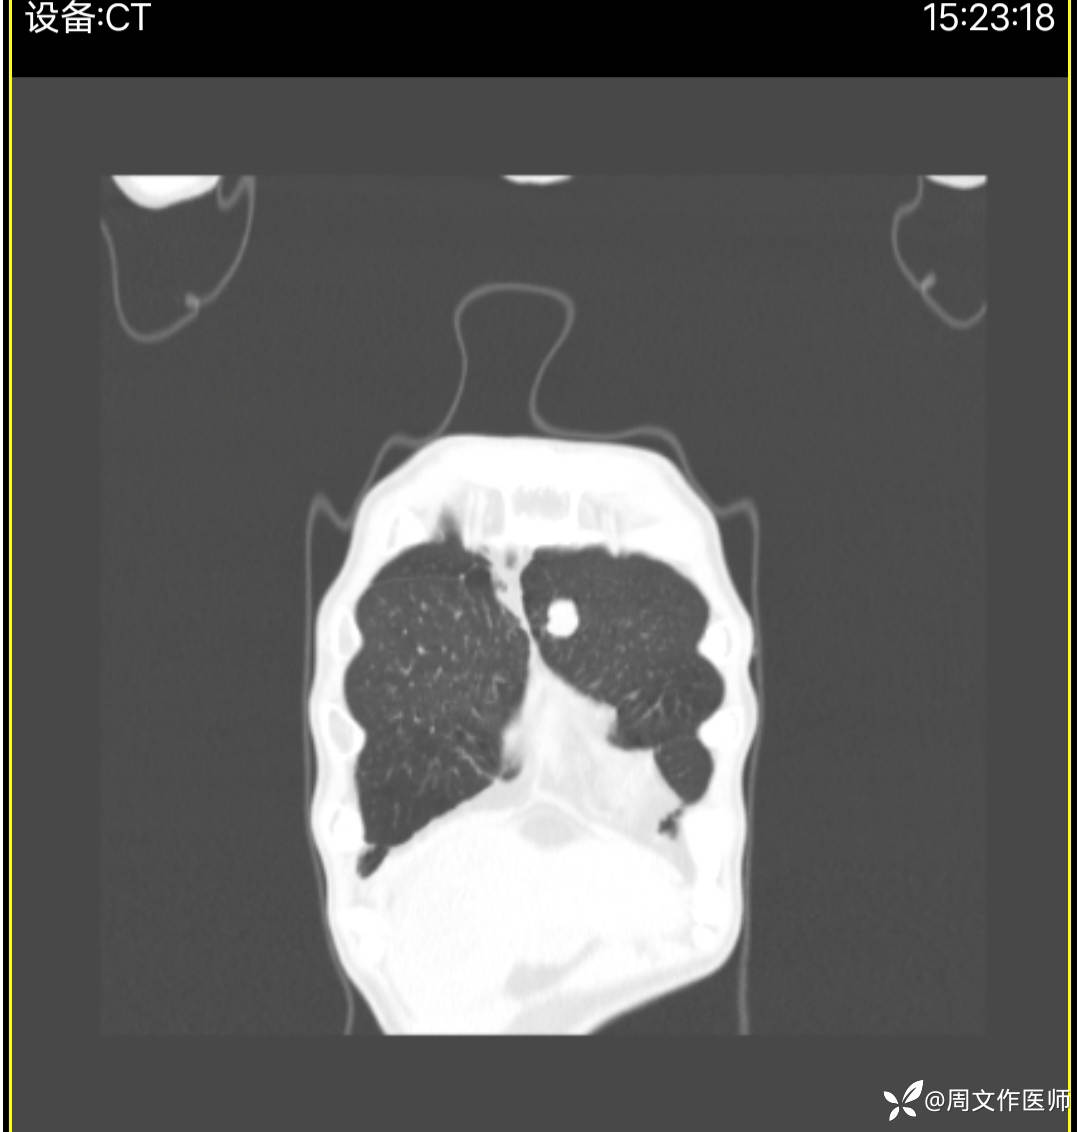

胸部CT检查